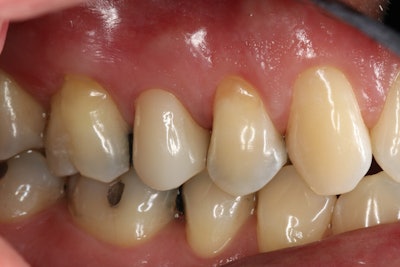

A 55-year-old man presented with pain upon biting and cold sensitivity along the gingival margin of tooth #4 (Figure 1). The patient reported taking medication for high blood pressure and experiencing job-related and personal stress, which contributed to his bruxism habit. He had been wearing a nightguard for the past five years to manage the effects of grinding.

Figure 1.